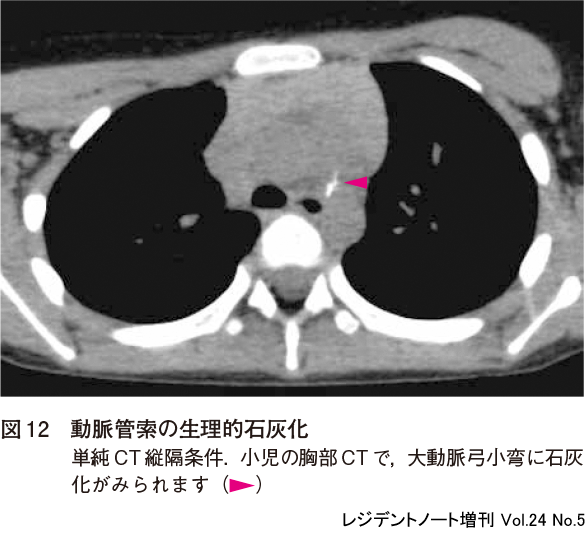

2)動脈管索の生理的石灰化

動脈管索に生理的石灰化(calcification of the ligamentum arteriosum)がみられることがあり(図12),石灰化は小児でも認められます.魚骨誤飲が疑われる小児に対して,胸部CTで咽頭や食道の魚骨異物を検索する際,魚骨と紛らわしい線状の石灰化を認めることがありますが,動脈管の解剖学的な位置から判断できます.